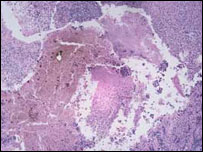

نمونه ای از سرطان پوست

هر يک از انواع سرطان پوست نشانه ها و عوارض خاص خود را دارند